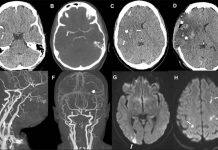

Covid-19 vaccine: Common stroke symptoms must be ‘urgently evaluated’

UCL and UCLH neurologists have published the first clinical observations of patients who experienced an ischaemic stroke, the most common form of stroke, following an Oxford AstraZeneca vaccine.